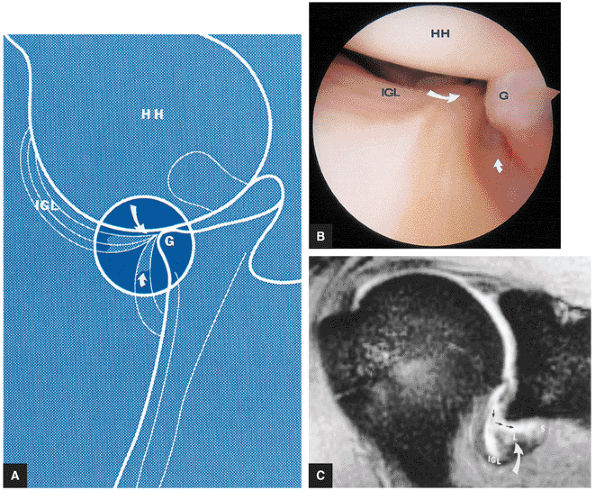

FIGURE 8.68 ● The biceps tendon (BT) contributes to the superior anterior labrum (AL) and the superior posterior labrum (PL) in the BLC. One component of the LHBT attaches to the supraglenoid tubercle. Extra-articular fibers attach to the lateral edge of the base of the coracoid process. The intra-articular portion of the LHBT is oriented at an approximate right angle to the surface of the glenoid (G). HH, humeral head; SGL, superior glenohumeral ligament.

|